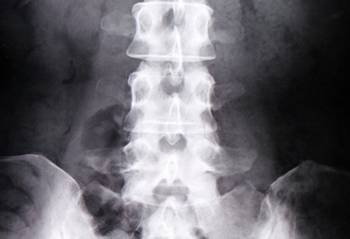

![骨密度検査装置(DEXA)[写真]](/toubu-clinic/images/clinic/pht_medical-treatment_dexa.jpg)

- 骨密度検査

私たちは、骨粗しょう症の予防と早期発見、治療に取り組んでいます。